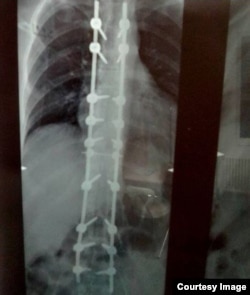

У Евгения из Алтайского края болезнь Бехтерева, поражающая позвоночник и грозящая неподвижностью. В 2018 году ему сделали операцию, установили на позвоночник титановую конструкцию, но лечение может лишь замедлять болезнь и повышать качество жизни. Евгению необходимо ежедневно несколько часов носить корсет полужёсткой фиксации с двумя металлическими пластинами, но его у него нет до сих пор.

Рентген-снимок позвоночника Евгения